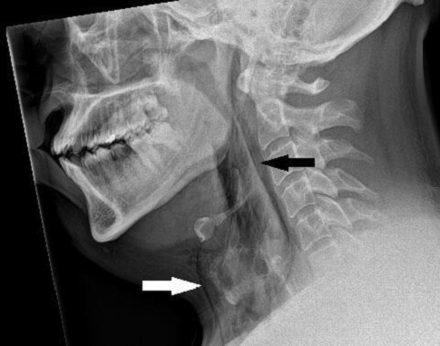

Розрив трахеї

В результаті, підвищився тиск у трахеї, і стався 2-міліметровий розрив.

Коли чоловіка доставили до медзакладу, його шия опухла з обох боків, але ковтання та мовлення не порушилися.

Лікарі виявили хірургічну емфізему – стан, коли повітря потрапляє під найглибші шари тканин.